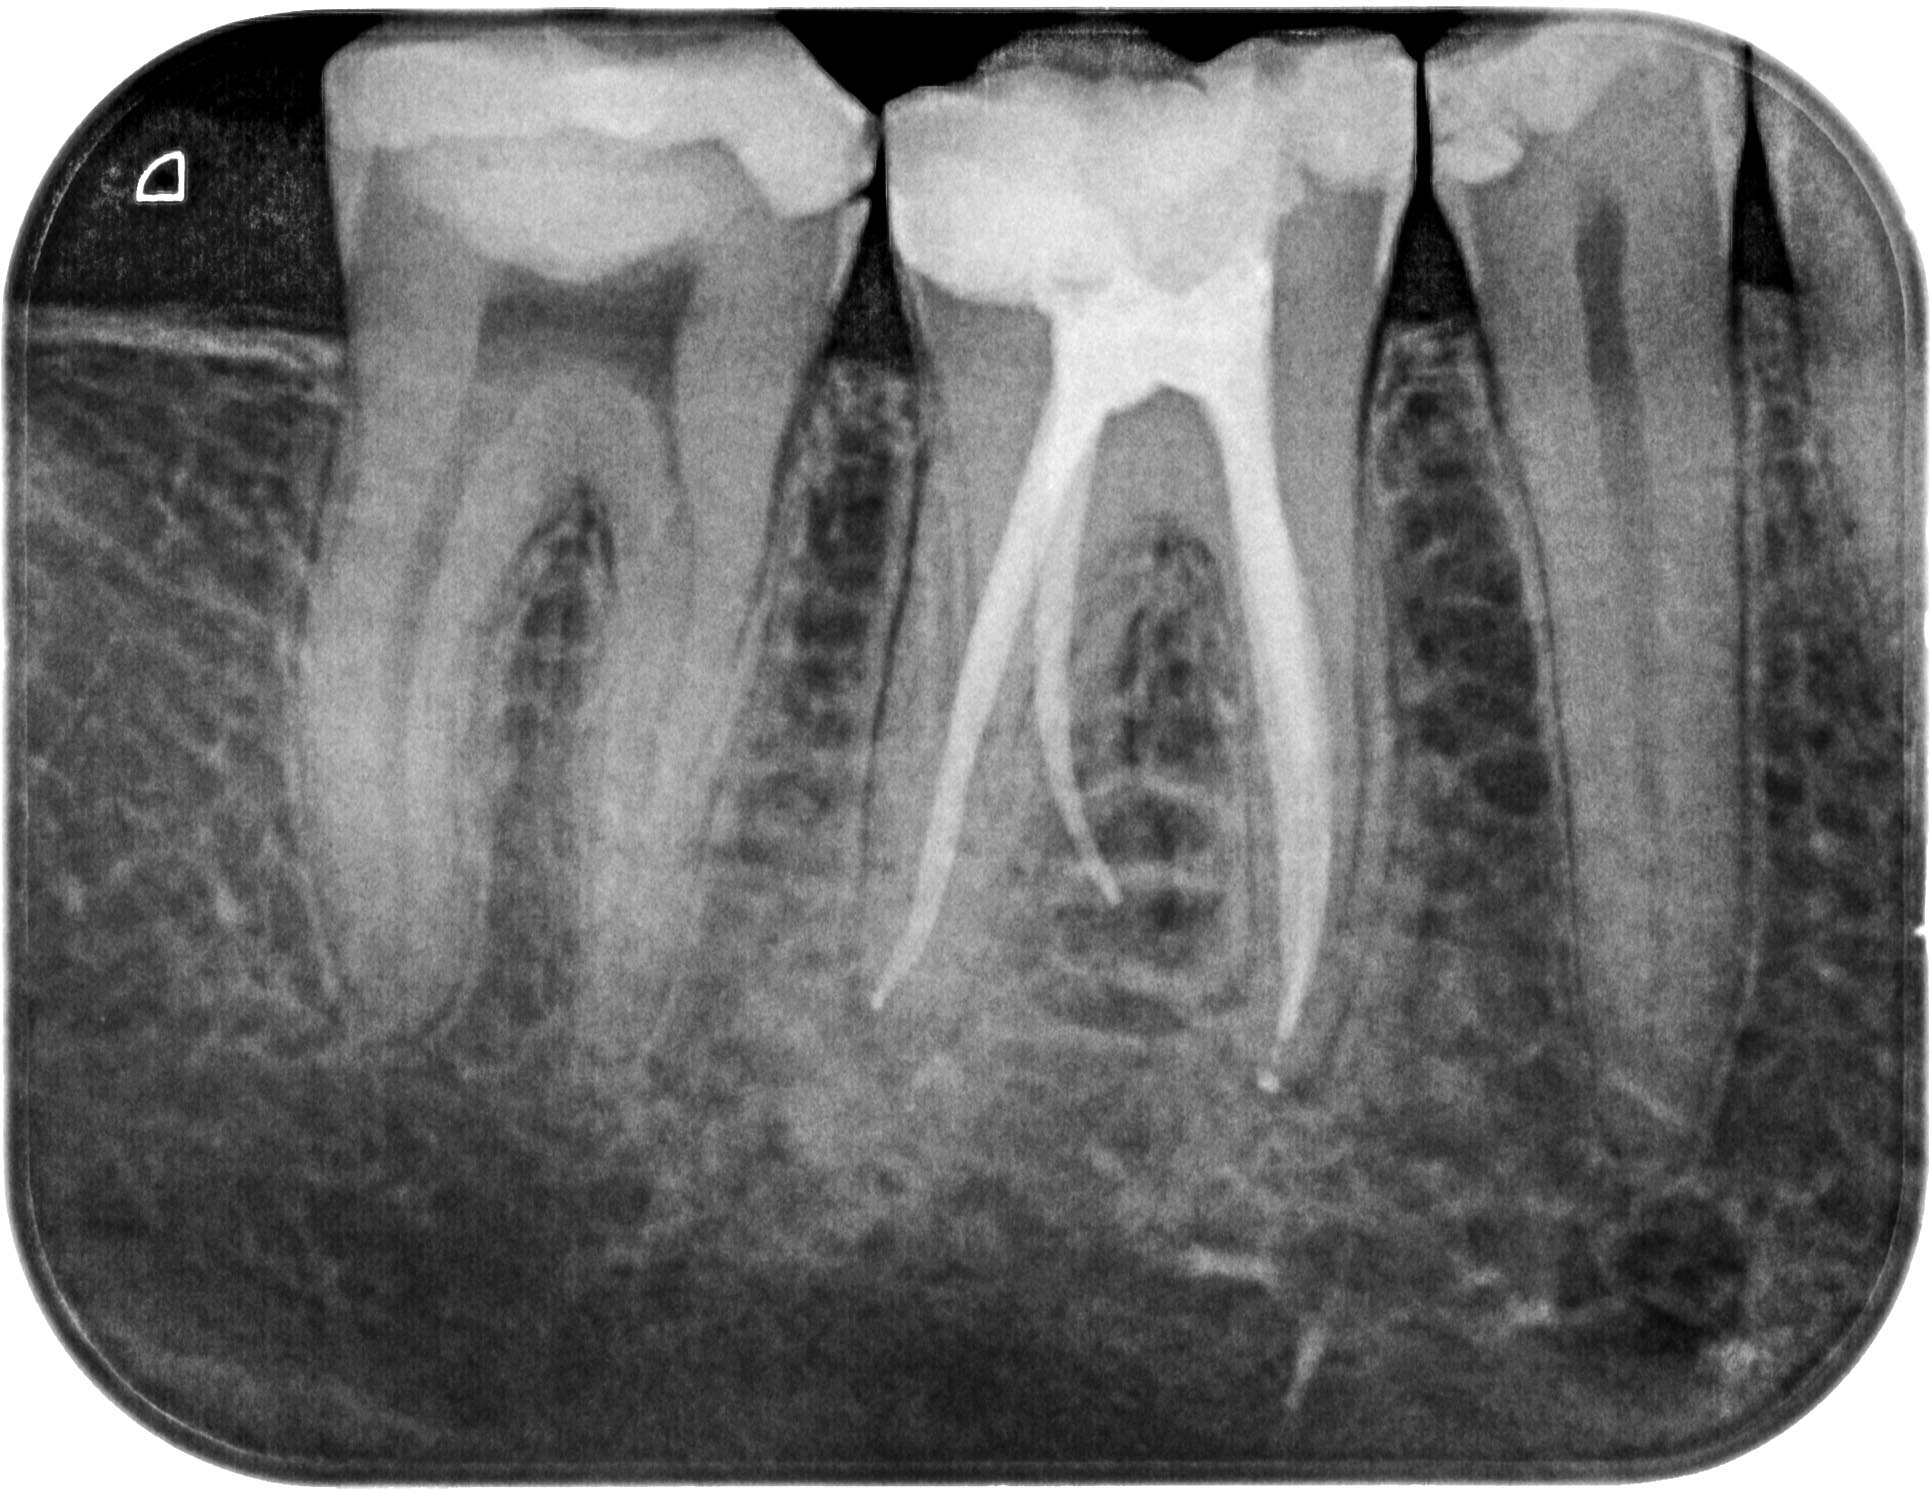

EP_46-1-3

1931 × 1489

Schwieriger UK- Molar (1 von 3)